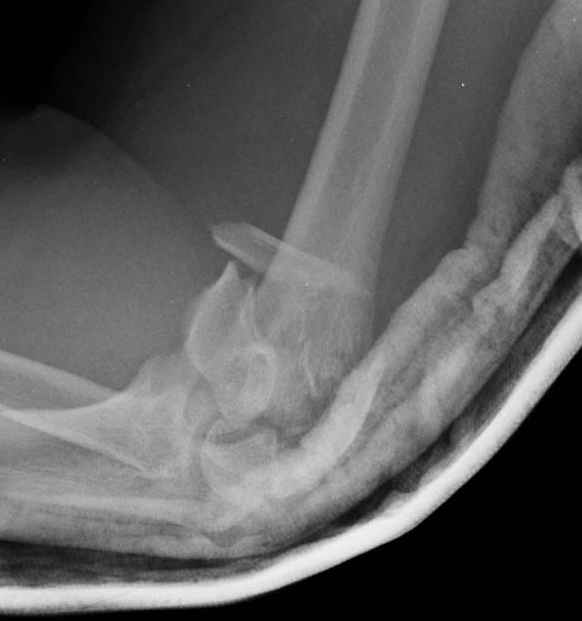

Примерный случай, только перелом был открытый, в задне-медиальной стороне рана около 2 см по характеру "изнутри кнаружи", неврологический статус со слабостью сгибания мизинца, также слабая абдукция и аддукция указательного пальца и сгибания в кисти.

Больному сделали обработку и наложили временный аппарат внешной фиксации плечо-предплечье.

Этапы операции на снимках....